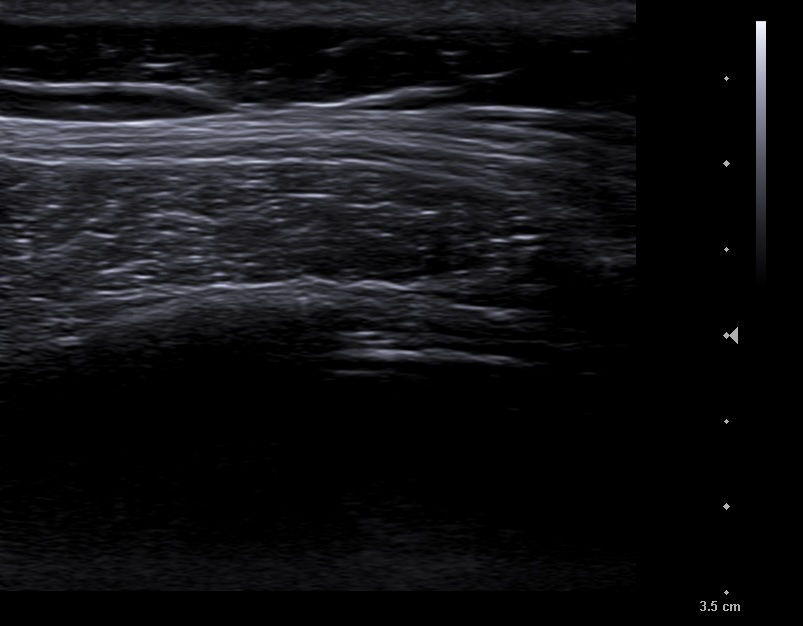

En la ecografía apreciamos en campo derecho un patrón ecográfico tisular, con líneas y puntos hiperecoicos, y algún artefacto en cola de cometa, correspondientes a broncograma aéreo.